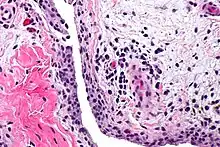

Chronic synovitis | |

Synovitis is the medical term for inflammation of the synovial membrane. This membrane lines joints that possess cavities, known as synovial joints. The condition is usually painful, particularly when the joint is moved. The joint usually swells due to synovial fluid collection.

Synovitis may occur in association with arthritis as well as lupus, gout, and other conditions. Synovitis is more commonly found in rheumatoid arthritis than in other forms of arthritis, and can thus serve as a distinguishing factor, although it is also present in many joints affected with osteoarthritis.[1][2] In rheumatoid arthritis, the fibroblast-like synoviocytes, highly specialized mesenchymal cells found in the synovial membrane, play an active and prominent role in the synovitis.[3] Long term occurrence of synovitis can result in degeneration of the joint.